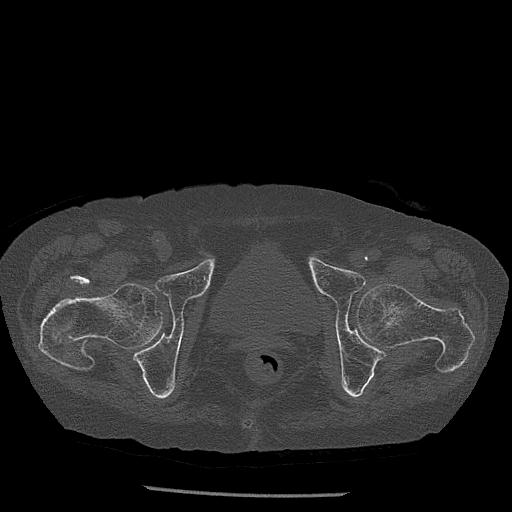

100703 1/27 両股正面+軸 1/29 両股正面+軸 94歳女性 パンソンロン